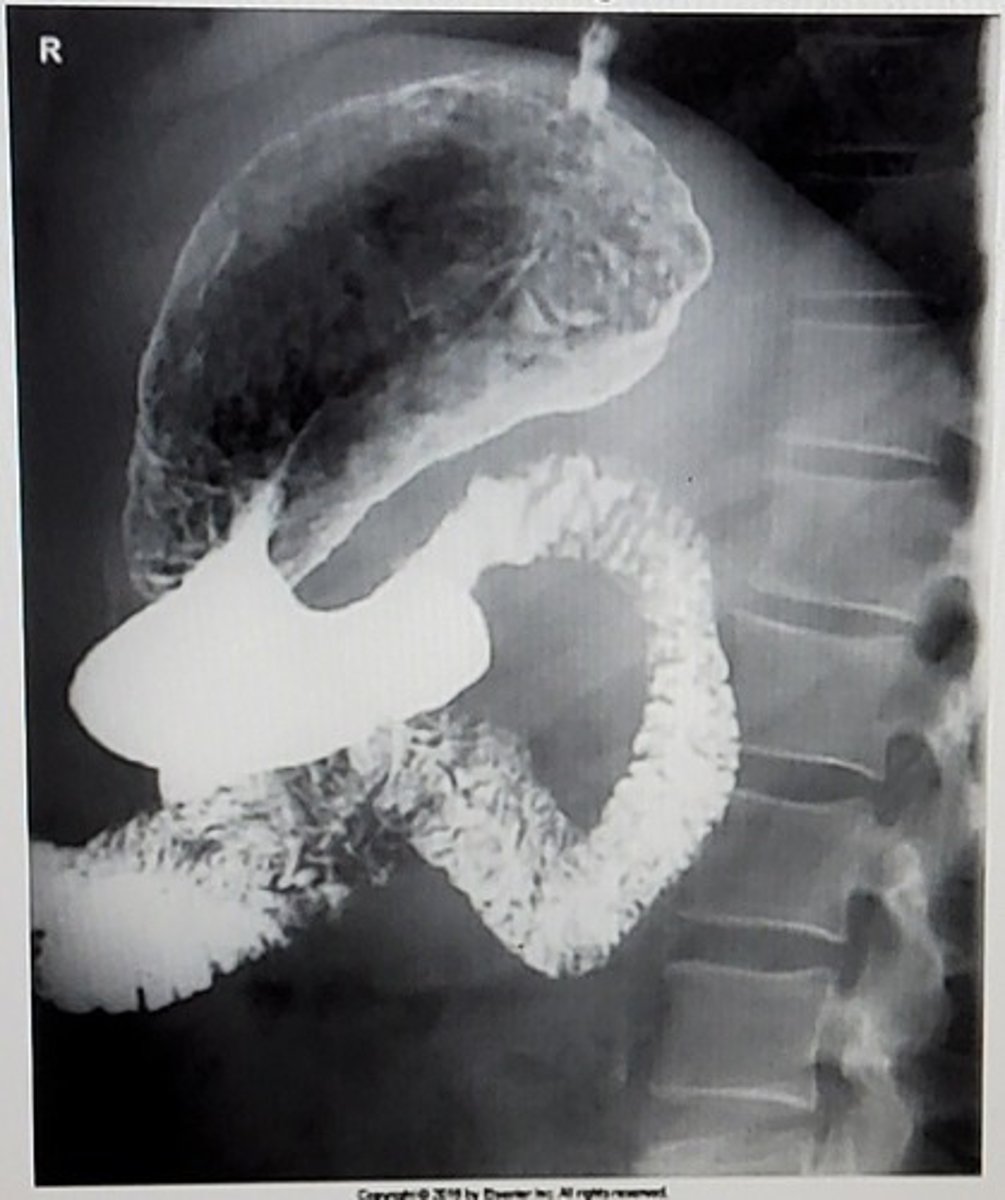

D. Right lateral

What position is this image?

A. RAO

B. AP

C. RPO